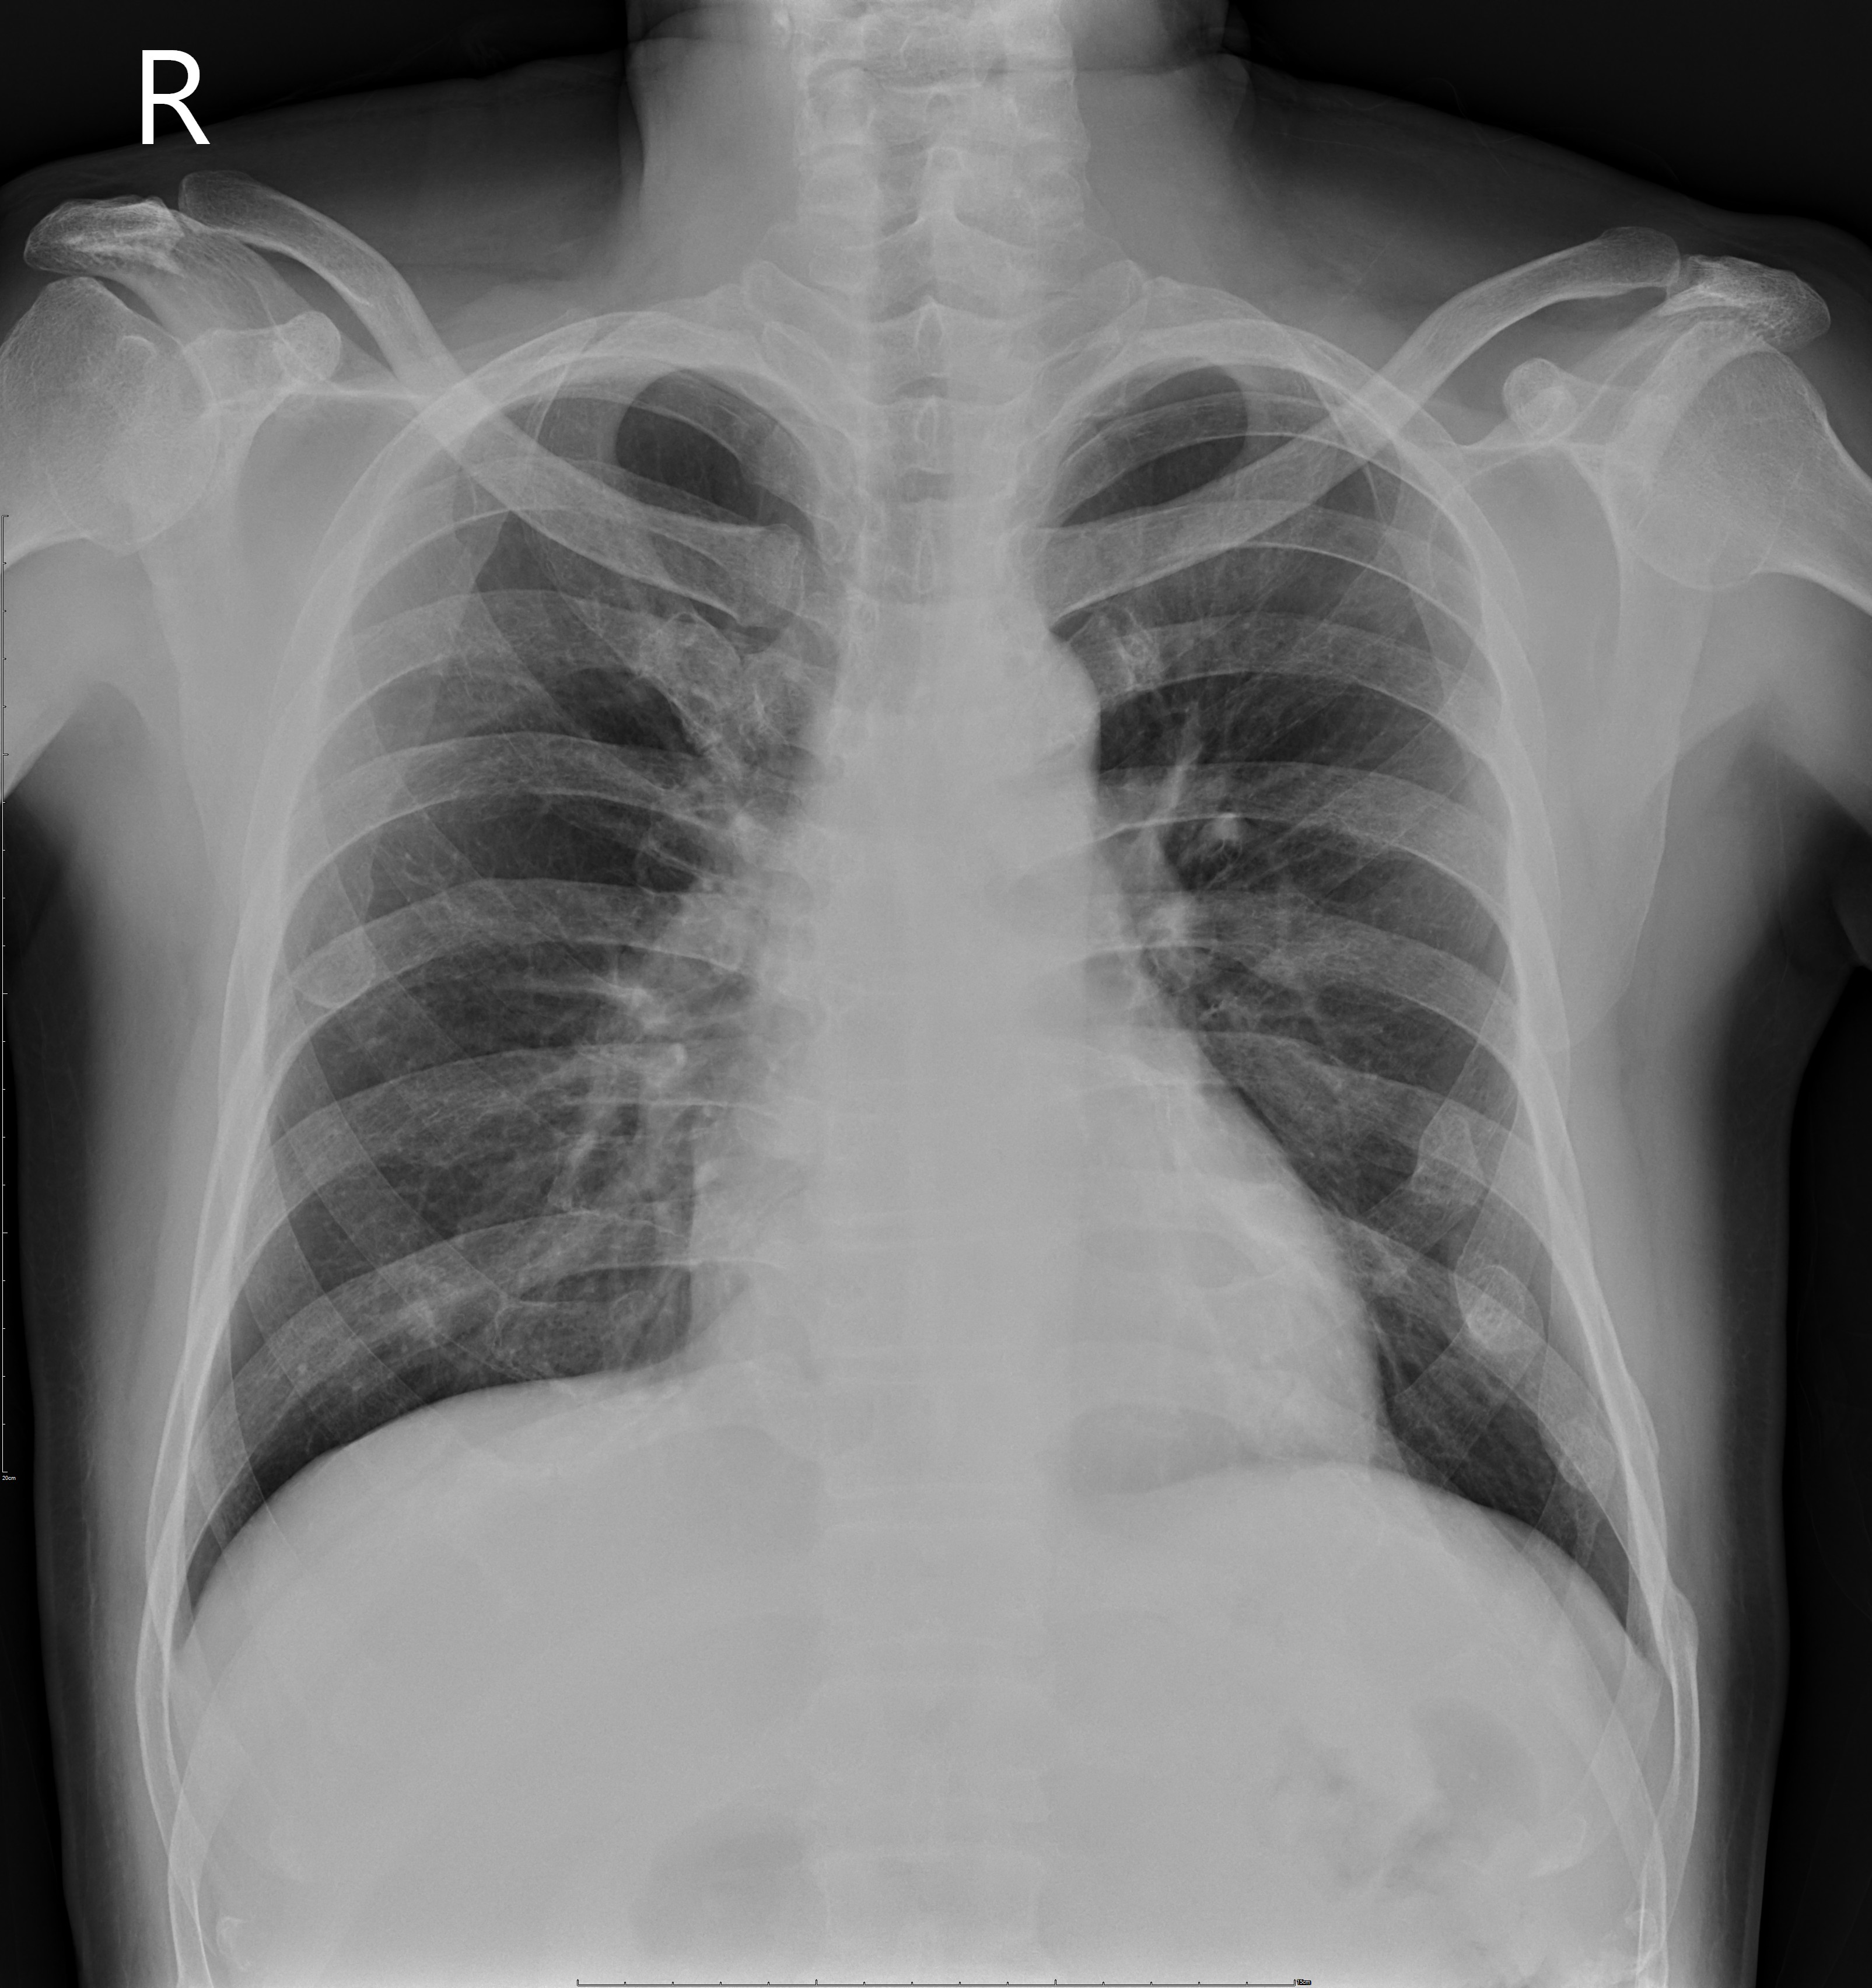

A 63-year-old male with a medical history of poorly controlled type 2 diabetes, hypertension, stage III chronic kidney disease, and a previous non-ST elevation myocardial infarction (NSTEMI) treated with drug-eluting stents, presented to the emergency department with recurrent chest tightness, which lasted approximately 10 minutes. Upon examination, his vital signs were stable, and his heart rhythm was regular with normal heart sounds and no murmurs. Lung auscultation was clear bilaterally.

Relevant Test Results Prior to Catheterization

EKG revealed normal sinus rhythm with myocardial ischemic change. Laboratory data demonstrated elevated cardiac enzyme and impaired renal function. Initial transthoracic echocardiography revealed anterior wall motion abnormality with impaired left ventricle systolic function.